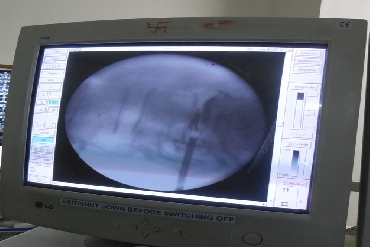

A herniated lumbar disc can push on spinal nerves and cause severe, shooting leg pain, numbness and/or weakness. A percutaneous disc removal (PDR) can remove a portion of the herniated disc that is compressing spinal nerves through a small incision in the skin. This minimally invasive approach uses a much smaller incision than traditional open spinal surgeries and avoids damage to the low back muscles.

In some cases, removing part of the herniated disc in a partial discectomy procedure can also prevent the disc from irritating the nerve.